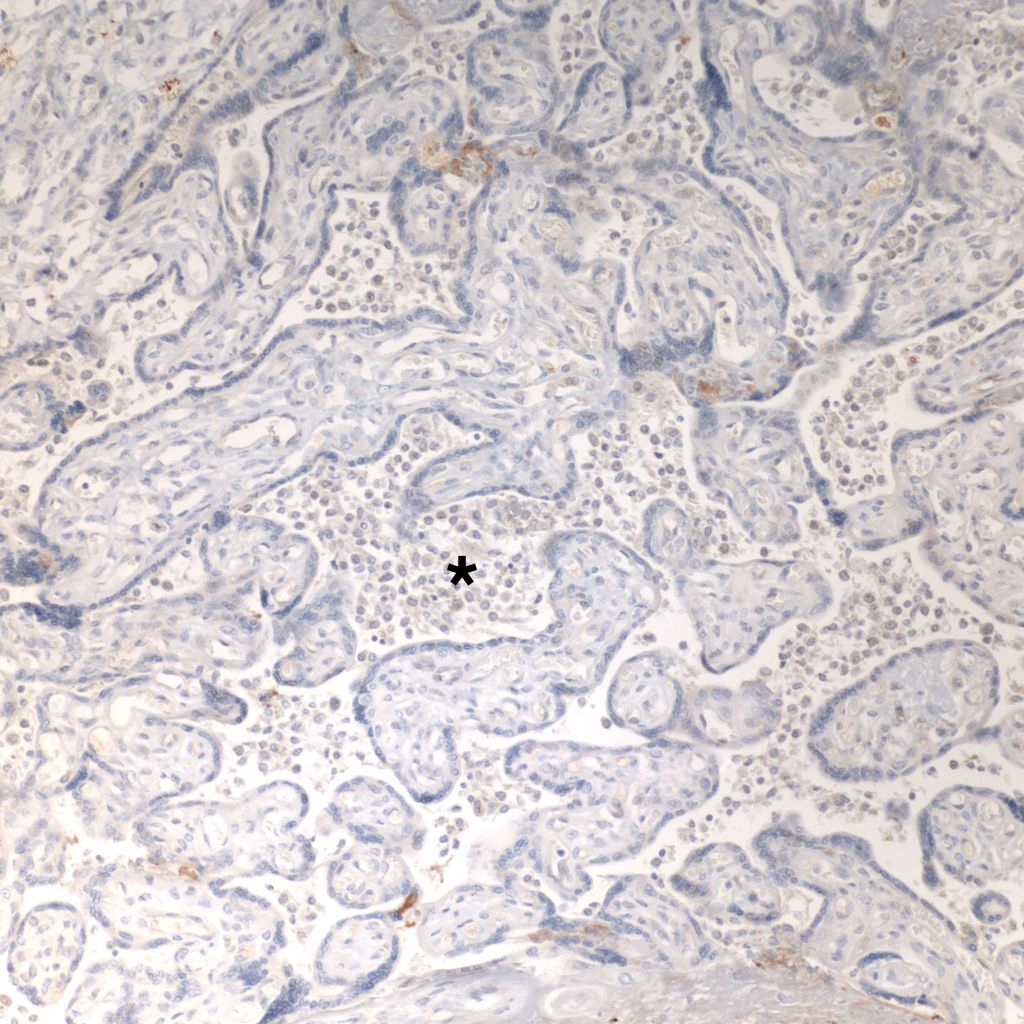

CD68 or alkaline phosphatase: to confirm that the intervillous cells are monocytes, but is not required for meeting the diagnostic criteria

C4d: to show evidence of complement fixation on the microvillous surface of the syncytiotrophoblast. While further study is needed, the subclassification of intervillous monocyte accumulations into those with and without complement fixation and the subclassification of villitis of unknown aetiology with intervillous monocytes into those with and without complement fixation may prove to be a useful distinction.

C4d: One study of CHIV compared 3 histologic groups of placentas demonstrating intervillous histiocytes: Few intervillous monocytes, massive intervillous monocytes, and intervillous monocytes associated with villitis of unknown aetiology18. Each group was further divided into subcategories based on the extent of c4d immunostaining of the microvillous surface of the syncytiotrophoblast. The outcome variables were fetal death or growth restriction. In the analysis, without a formal ROC study, it appeared that staining less than 25% of the villous surface was a natural cut off point from greater than 25%. As can be seen in the Table 1 of the raw data, that with rare exceptions, all the cases with less than 25% of c4d trophoblast staining, and often without any staining, were either associated with few intervillous monocytes, or with villitis. Fetal death or growth restriction was almost always associated with more than 25% of the villous surface stained with c4d. The lack of statistical significance in the comparisons is likely due to small sample size.